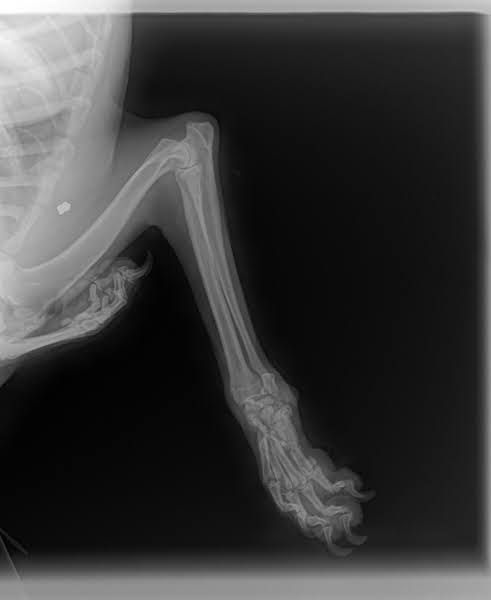

Bemerkungen: Scotti hat Probleme mit seiner Pfote, denn auf ihn wurde geschossen.

Auf Scotti wurde geschossen. Er wurde schwer an der Vorderpfote verletzt und er wurde dann auch einfach liegen gelassen. Glücklicherweise wurde der Tierschutz verständigt und Scotti wurde direkt in ärztliche Obhut gebracht. Dies alles geschah in der zweiten Januarwoche 2025.

Die Genesung von Scotti dauerte sehr lange, aber alle Bemühungen haben sich gelohnt und Scotti hat auch alle Anwendungen brav und geduldig ertragen. Die Verletzung ist aktuell verheilt, aber Scotti wird wohl sein ganzes Leben humpeln.